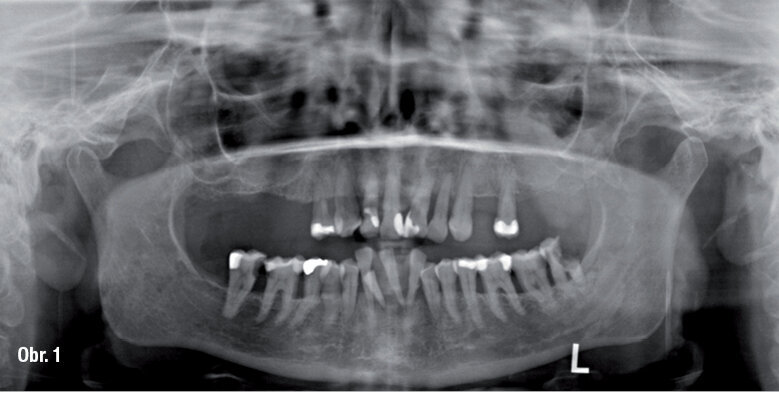

V druhé fázi proběhla extrakce zbylých zubů v dolní čelisti se současnou implantací (CAMLOG Implantate), augmentací zbytku alveolárního hřebene a zavedením dočasných implantátů do oblasti 33 a 43 v jednom kroku s připevněním dolní imediátní náhrady.

OPG snímek se 16 zavedenými implantáty a augmentovanými oblastmi